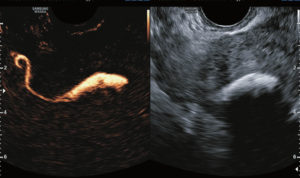

УЗИ ГСГ маточных труб проводят приблизительно на пятый – десятый день менструации. В матку вставляется катетер, через который вводят контрастное вещество. Этот препарат поступает и в трубы. Это улучшает их визуализацию.

Таким образом врач может осмотреть особенности строения труб. Контраст продолжает вводиться и далее поступает в полость брюшины. Это указывает на хорошую проходимость труб.

Если жидкость не может достичь брюшной полости, это означает, что проходимость нарушена.

При обычном УЗИ трубы матки не получается визуализировать. Для их осмотра всегда вводят контраст, которым наполняется матка, он затем продвигается далее по трубам. Если проходимость хорошая, то врач наблюдает за этим процессом.

Сама процедура не занимает много времени. Она длится около 15 минут. Исследование начинается с того, что в матку надо ввести тонкий катетер. По нему поступает контрастное вещество (количество – около десяти миллилитров) в полость органа.

В качестве контраста может выступать физраствор, глюкоза, также это может быть фурацилин, используются и другие жидкости. Трансвагинальный датчик передаёт изображение на дисплей, которое визуализируется в формате 3D.

Врач осматривает матку и её структуру, трубы.

Хорошая проходимость отмечается фактом поступления жидкости в полость брюшины, а затем её всасыванием в кровь.